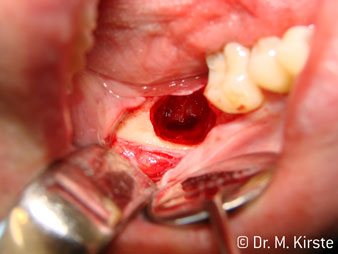

Le contre-angle avec tête angulée à 45° a surtout été choisi pour ses nombreux avantages. Les collègues qui exercent en chirurgie, et à qui cet instrument est principalement destiné, apprécieront très vite la possibilité de travailler efficacement dans des zones très étroites. En particulier, lors d’extractions de dent de sagesse (Ill. 2), où il n'y a pas besoin d’un grand angle d’écartement des tissus mous dans la région de la joue (Ill. 3). Pendant la préparation, une légère rotation de la tête de l’instrument permet un travail rapide et sans risque dans la zone rétromolaire.

La conception particulière des roulements à l'intérieur de la tête du contre-angle garantit un fonctionnement silencieux de l’instrument rotatif et lui procure une grande efficacité de coupe, sans à-coup ; ce qui est appréciable lors des interventions chirurgicales comme par exemple les séparations dentaires et résections apicales (Ill. 4-9).

Le contre-angle avec tête angulée à 45° est très agréable à utiliser. D’emblée on remarque que la partie travaillante de la tête imite l'angle de l’index et qu’ainsi le mouvement que vous souhaitez faire est simplement déplacé de deux ou trois centimètres, parallèlement à la pointe de l’instrument rotatif.“ (Ill. 1)